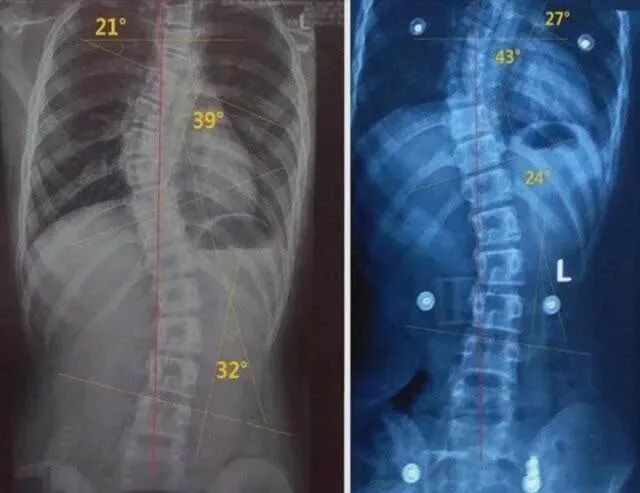

示意圖脊柱側(cè)彎,不僅會(huì)影響孩子的形體美觀,還會(huì)造成肌肉緊張,就是上邊說(shuō)的背痛的發(fā)生。坐著也不舒服,躺著也不舒服。當(dāng)脊柱側(cè)彎嚴(yán)重的時(shí)候,就會(huì)造成神經(jīng)損害,壓迫肺部,甚至出現(xiàn)影響呼吸的癥狀,有的還會(huì)出現(xiàn)脊柱的變形、增生等,導(dǎo)致椎管的狹窄,進(jìn)而產(chǎn)生腰疼和下肢的一些不適癥狀。

連主任告訴我們,脊柱側(cè)彎是一種復(fù)雜的脊柱三維立體扭轉(zhuǎn)異常, 事實(shí)上,只有極少數(shù)嚴(yán)重的脊柱側(cè)彎患者才需要進(jìn)行手術(shù)治療,絕大部分的輕中度脊柱側(cè)彎可以通過(guò)保守治療控制側(cè)彎進(jìn)展甚至得到完全糾正。而且是越早進(jìn)行積極的干預(yù)和治療,其治療效果越好。示意圖